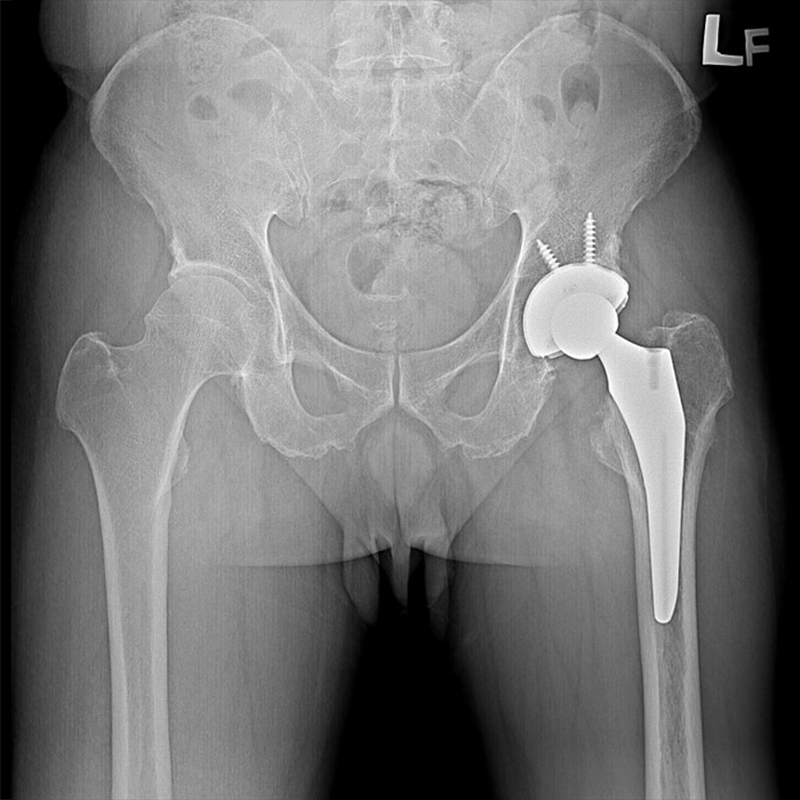

機器手臂手術 首頁 案例分享 髖關節手術 機器手臂手術 72歲 楊女士 退化性關節炎 術前 術後 60歲 彭先生骨股頭壞死 術前 術後 53歲 王女士退化性關節炎(DDH先天發育不全 CROWE TYPE 2) 術前 術後 83歲林女士退化性關節炎 術前 術後 83歲林女士退化性關節炎 術前 術後 楊女士 70歲 術前 術後 蔡女士 60歲 術前 術後